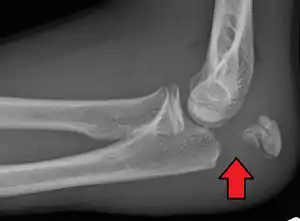

People with olecranon fractures present with intense elbow pain after a direct blow or fall.[1] Swelling over the bone site is seen and an inability to straighten the elbow is common. Due to the proximity of the olecranon to the ulnar nerve, the injury and swelling may cause numbness and tingling at the fourth and fifth fingers.[1] Examination can bring out a palpable defect at the site of the fracture.[2]

To assess an olecranon fracture, a careful skin exam is performed to ensure there is no open fracture. Then a complete neurological exam of the upper limb should be documented.[5][2] Frontal and lateral X-ray views of the elbow are typically done to investigate the possibility of an olecranon fracture.[1] A true lateral x-ray is essential to determine the fracture pattern, degree of displacement, comminution, and the degree of articular involvement.